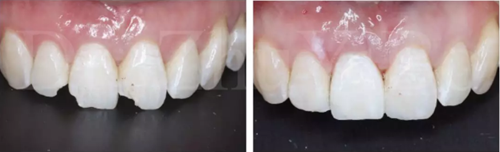

圖16 即刻修復(fù)后,患者恢復(fù)了美觀

即刻種植&即刻修復(fù)屬于高技術(shù)敏感性的操作,一旦出現(xiàn)美學(xué)并發(fā)癥往往很難處理,所以,要做好美學(xué)區(qū)即刻種植一定要從術(shù)前設(shè)計(jì)、病例選擇入手,全面考慮影響即刻種植美學(xué)效果的關(guān)鍵因素,在掌握好必備的知識(shí)與技能后,再?lài)L試即刻種植的治療。